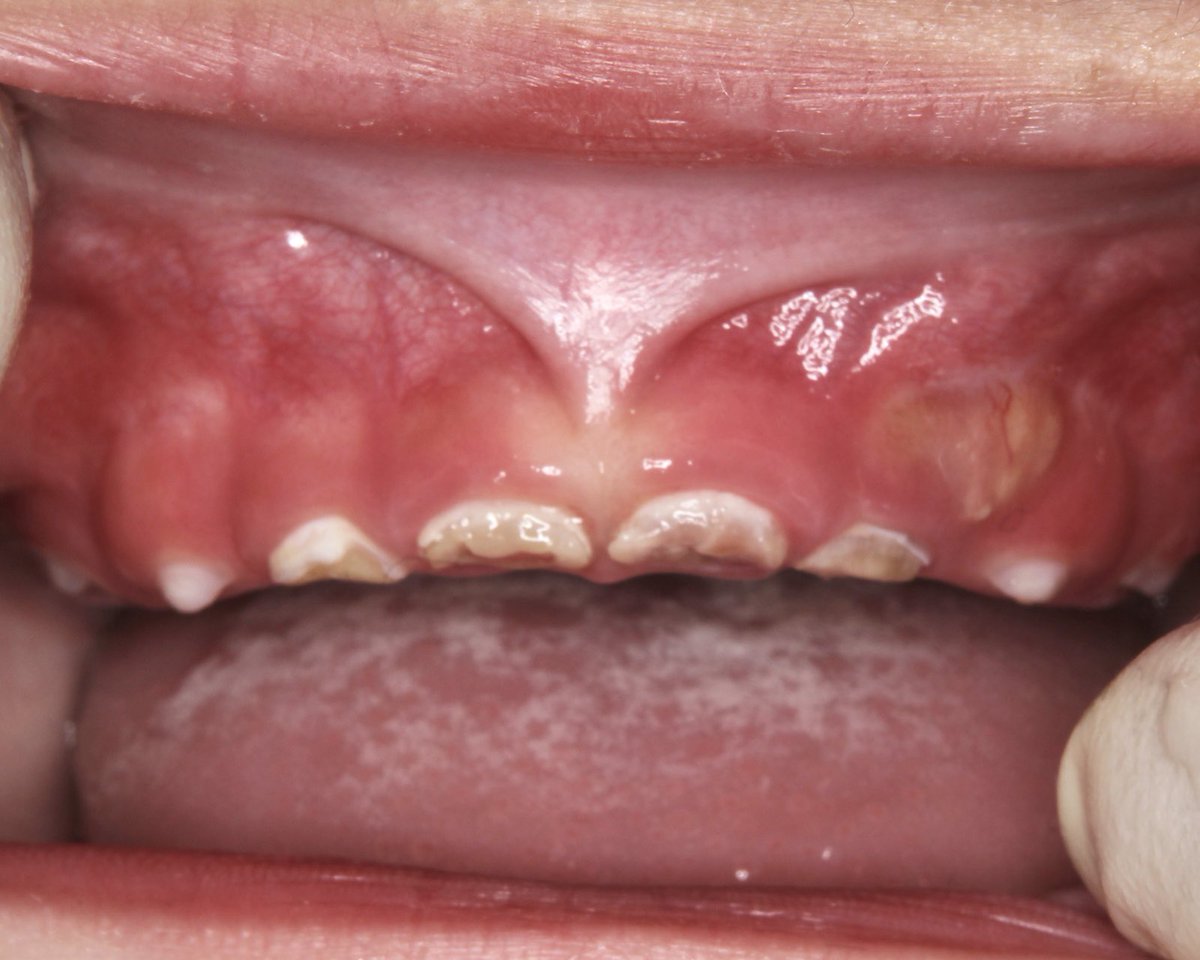

低年齢児の重度虫歯(むし歯)の背景にはジュースの常飲があることが多い。 (もちろんそれだけが原因ではないが) 治療は可能だが困難。 治療する歯科医師もされるお子さんもたいへん。 こんな世界があることをグリコなど飲料メーカーの方々がご存知なら安易な発信はできないはず。 #ジュース #虫歯